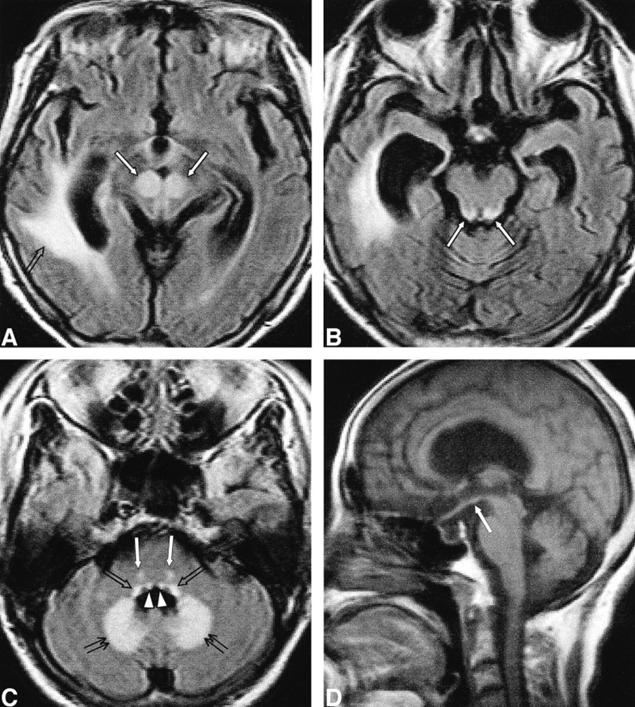

男,54歲,白血病病史。臨床表現(xiàn)為意識障礙、共濟失調。Flair示高信號位于雙側舌下神經(jīng)核(A)、前庭神經(jīng)內側核(B)、面神經(jīng)核(長箭頭)和展神經(jīng)核(短箭頭)(C)、中腦頂蓋和導水管周圍灰質(D)、乳頭體(E)、下丘腦和第三腦室周(F)。

病例4